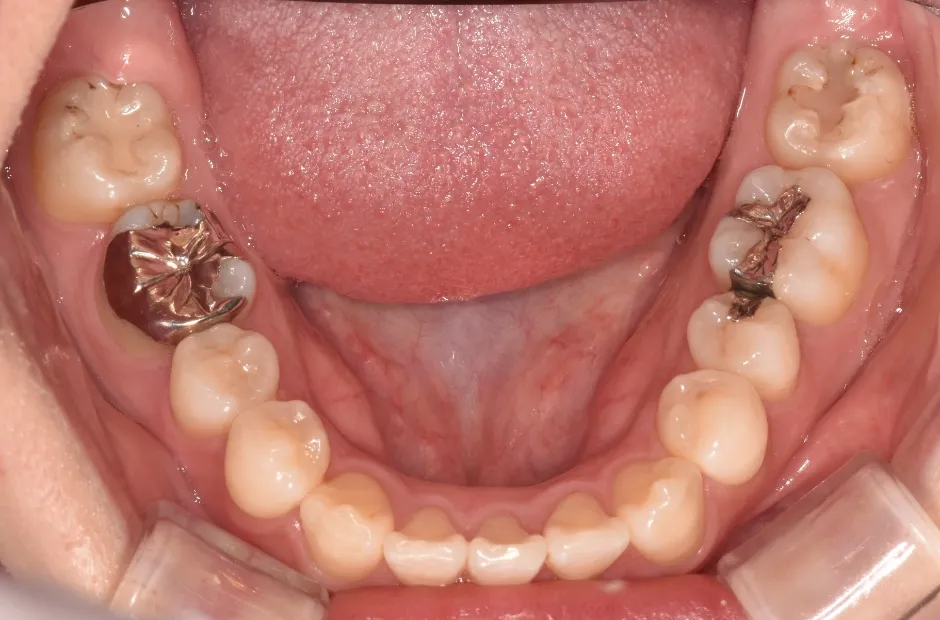

先天欠如(左右下2番)

| 診断名・主訴 | 過蓋咬合、出っ歯 |

|---|---|

| 年齢・性別 | 20歳・女性 |

| 治療期間・回数 | 2年 24回 |

| 治療に用いた主な装置 | 急速拡大 アンカー 2×4ワイヤー |

| 抜歯部位 | 左右上4番 |

| 治療費 | 70万円(税抜) |

| リスク・副作用 | 装置による違和感・疼痛・歯肉退縮・歯根吸収・虫歯のリスクなど |

治療前